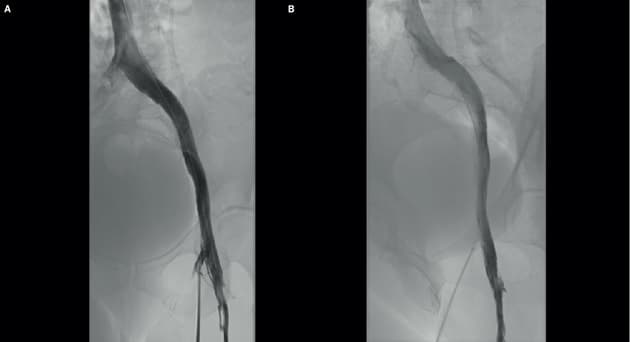

Digital subtraktoinsflebografi. (Ugeskr Læger 2021;183:V01210067)

Posttrombotisk syndrom forekommer hyppigt efter dyb venetrombose og kan være årsagen til smerter, hudforandringer og sår. Artiklen af Schmidt et al gennemgår patofysiologien, diagnostikken og behandlingen med fokus på endovaskulær behandling som ballondilatation og stentning. Forfatterne konkluderer, at stentning af bækkenvenerne medfører signifikant symptomlindring og bedre heling af venøse sår.